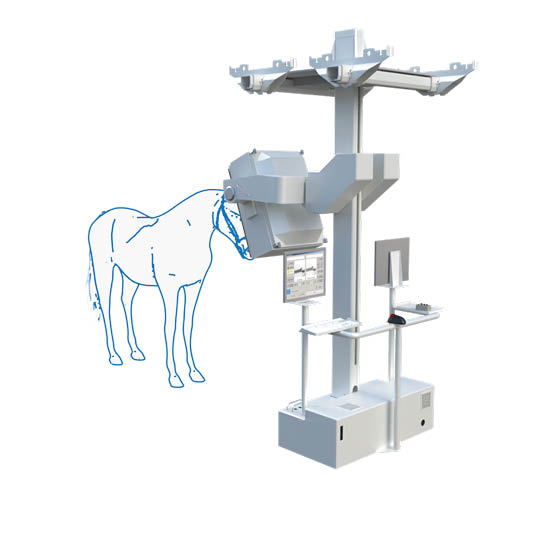

Scintigraphy on a Standing Horse

An ingenious combination of mechanics, electronics, and software makes scintigraphy on a standing horse easily achievable. Experience gained from human medicine, including detector specifications, measurement methods, and processing, as well as feedback from our many customers, has enabled us to achieve the goal of easy and fast diagnosis.

It is compact, robust, and mechanically superior to pendulum suspension systems. The detector support column is mounted approximately one centimeter above the floor, allowing quick and easy movements along any axis of the gantry support. Thus, the gantry operates at a low noise level.